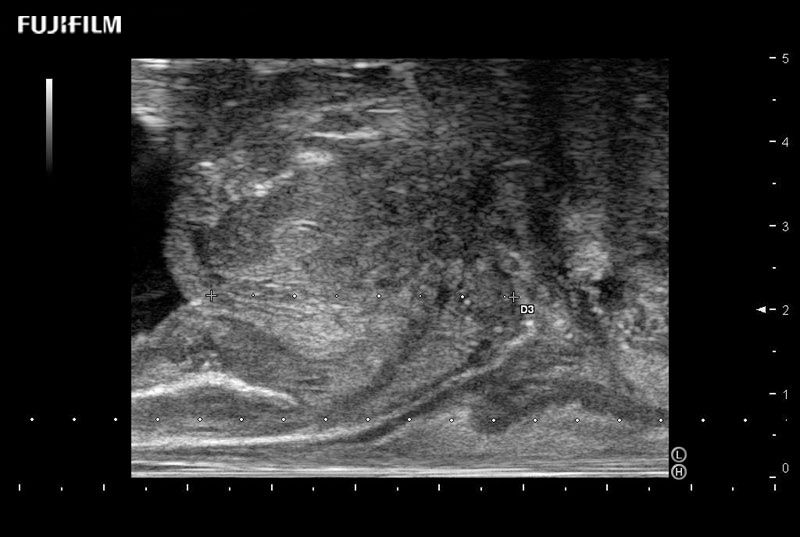

Ideal transducer for Transperineal Biopsy, Hydrogel Spacer Placement, Brachy LDR & HDR, Cryo, and MPMRI procedures.

Main Specifications: